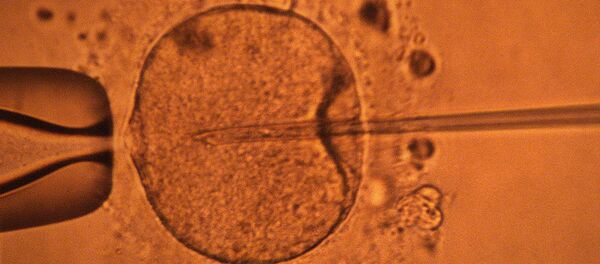

Սա աղջկա առաջին հաղթանակը չէ։ Կարինան Լոս Անջելեսում անցկացվող միջազգային մրցույթի արդյունքում արդեն պարգևներ ստեցել է։ Այնտեղ նա լավագույնն է ճանաչվել ուռուցքաբանության բնագավառում իր ուսումնասիրության համար։ Այն ժամանակ նա ներկայացրել էր ԴՆԹ–ի մուտացիաների և RAD51 պրոտեինի մասին իր աշխատությունը («RAD51 protein mutations in the development of cancer» (The role of RAD51 mutations in cancer development)։ Աղջիկը քաղցկեղային բջիջների զարգացումը կանխարգելող մեխանիզմ է հայտնաբերել։